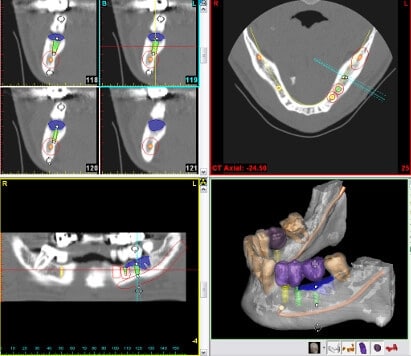

Die computergestützte 3-D-Implantatplanung nennt man auch navigierte Implantologie. Die Navigation beim Einsetzen der Zahnimplantate erfolgt mithilfe einer Bohrschablone oder auch Navigationsschablone, die auf den Datensätzen der 3-D-Diagnostik beruht. Der Implantologe oder die Implantologin erhält durch die 3-D-Diagnostik hochauflösende Bilder, die eine gestochen scharfe 3-D-Ansicht des Kiefers liefern. Ob Knochen, Nerven oder Blutgefäße – alles ist gut sichtbar. Der Oralchirurg ist dadurch bestmöglich über die Gegebenheiten im Kiefer informiert und kann aufgrund der vorhandenen Daten die Länge, den Durchmesser und den Neigungswinkel des Implantats unter besten Voraussetzungen planen. Die vorhandene Knochensituation kann optimal genutzt werden. Das ermöglicht einen insgesamt schonenderen, schnelleren und sichereren Ablauf bei der minimalinvasiven Implantation.